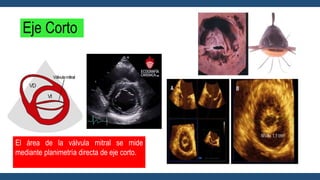

Eje Corto

El área de la válvula mitral se mide

mediante planimetría directa de eje corto.